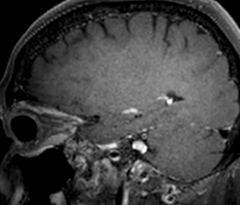

The abbreviated MS protocol for brain is only around 9 minutes, so in case of suspected multiple sclerosis, one or two more advanced sequences may be added, such as PSIR (phase sensitive inversion recovery) or susceptibility-weighted sequences to help us make more confident diagnoses in these inflammatory cases.

In this example, the optional 3D multishot susceptibility weighted sequence with 0.6 mm isotropic voxels is 2 lesions with a central vein sign (arrows) and one lesion with a phase-rim sign (arrowhead). The total scan time, including SmartBrain and axial PD/T2 3mm, is 11:10 min. and is 18:30 min. with the optional 3D PSIR and 3D SWI multishot included.

“We used to have long examination times for certain types of patients, a few lasting more than 40 minutes,” says Dr. Savatovsky. “What is remarkable, is that now all these examinations are below 30 minutes, which opens up opportunity to add more sequences when needed. It’s really hard to keep a patient for more than 40 minutes in the scanner, but because we have now cut scan times by at least 10 minutes, we can add more sequences without making the exam too long. And this is where the new system helps us make a difference. Examples include our examinations for informing brain tumor classification or giant cell arteritis workup, or for intracranial wall imaging – so in patients where we need several advanced sequences or high resolution sequences.” “We added three additional sequences in our brain neoplasm classification exam: a 3D SWI sequence, APT and ASL on top of 3D morphologic sequences, an isotropic DSC (dynamic susceptibility contrast) and multivoxel spectroscopy. I think that in patients that need a classification for brain mass, for example, we can provide a more detailed and confident diagnosis than before, allowing the clinicians to decide for either a medical workup if no tumor is suspected, or for neurosurgery as soon as possible if a neoplasm is suspected.” “In multiple sclerosis patients, we increasingly include a multishot susceptibility sequence [3] in our routine cases, thanks to the shorter scan times. Our abbreviated MS protocol for brain is around 8 to 9 minutes, so we can ask for one or two additional sequences to visualize the central veins, or to get an additional contrast to better depict posterior fossa lesions. In cases of white matter lesions of unknown significance on FLAIR images, for example when we see high signal hyperintensities in the brain, we can add on more advanced sequences such as PSIR (phase sensitive inversion recovery) or susceptibility-weighted sequences to help us in distinguishing between MS and nonspecific or vascular abnormalities in these inflammatory cases.”